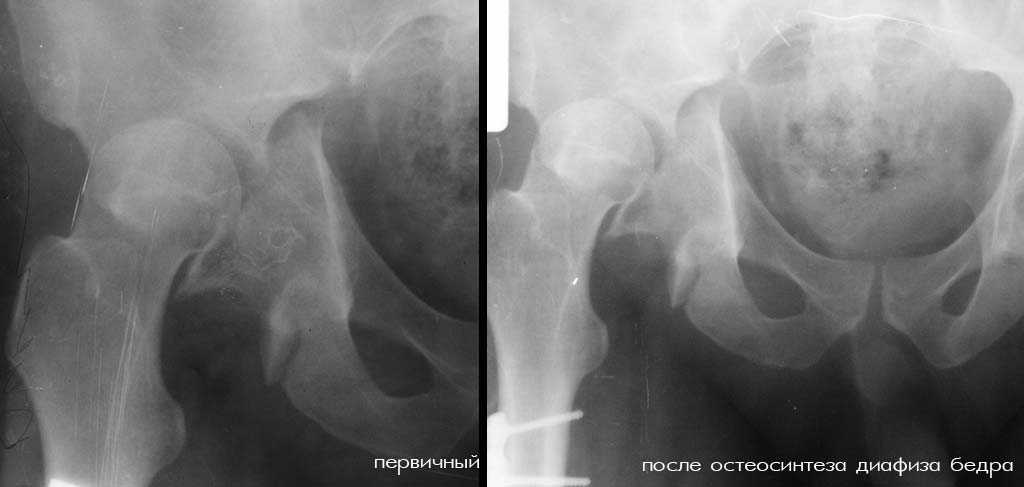

К нам переведен больной 36 лет (175 см рост, 105 кг масса тела), который 64 дня назад в ДТП получил множественную скелетную травму: перелом вертлужной впадины справа с задним вывихом бедра и повреждением крестцово-подвздошного сочленения справа, оскольчатым (тип C3) переломом диафиза правого бедра на границе с/3 - н/3, открытый (тип III В по Каплану-Марковой) краевой перелом мыщелков правой большеберцовой кости, закрытый поперечный перелом диафизов костей правой голени на границе с/3-н/3 (т.е. все повреждения справа). Судя по анамнезу, имело место сдавление правой голени и бедра около 1,5 часов. В ЦРБ (по месту получения травмы) был доставлен в тяжёлом травматическом шоке, отмечались признаки ОПН (в частности, олигурия и подъём уровня креатинина выше 300 ммоль/л). Судя по анамнезу, более месяца сохранялся резко выраженный отёк правого бедра. Из выписки известно, что безуспешные попытки закрытой репозиции вывиха бедра были выполнены при поступлении в ЦРБ. Больному также выполнен накостный остеосинтез диафиза правого бедра. Рана зажила первичным натяжением. Голень фиксирована гипсовой повязкой. В области правого коленного сустава остаётся обширная рваная рана с дефектом кожи (до 20x20 см), частично закрытая дерматомными лоскутами, из которой высевается полирезистентный acinetobacter. Продолжает эпизодически лихорадить (до 38), сохраняется лейкоцитоз (11-14 тыс), в ряде анализов крови отмечался сдвиг до миелоцитов (1-6%). В остальном - без видимой патологии. Отёк бедра в настоящее время незначительный. После перевода наложено вытяжение за бедро 12 кг. Хотелось бы узнать мнения о вариантах тактики лечения перелома вертлужной впадины и вывиха бедра (учитывающие и давность травмы, и сопутствующие повреждения). Хотя этот нюанс совсем немедицинский, но замечу, что больной не настроен на любые виды платной медицинской помощи. Имеющиеся рентгенограммы и КТ приложены. С уважением Игорь

К сожалению, отправить все снимки и КТ сразу не получилось. Дополняю.

Я за агрессивную тактику- молодой пациент с поперечным трансвертлужным переломом таза,перелом задней стенки впадины с вывихом бедра+наружная ротация проксимального отломка таза с повреждением lig.sacroiliac interosseous anterior.Конечность в наружной ротации,как нерв?

Скорее всего перелом Т-образный и головка вроде бы цела. Я бы разобрал впадину и собрал обратно с фиксацией трансфрактурными винтами передней колонны и мостовидной пластинкой задней. Перед открытой реконструкцией возможно наложил бы аппарат таз бедро для низведения головки, если пластина на бедре выглядит надежной.